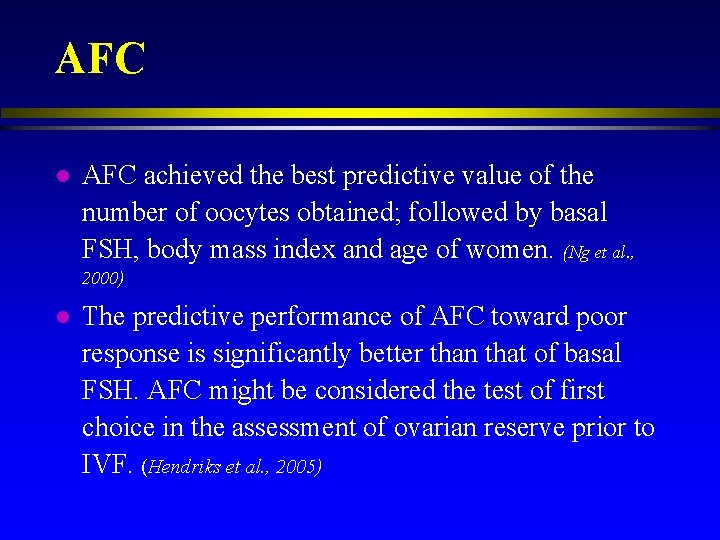

AFC l AFC achieved the best predictive value of the number of oocytes obtained; followed by basal FSH, body mass index and age of women. (Ng et al. , 2000) l The predictive performance of AFC toward poor response is significantly better than that of basal FSH. AFC might be considered the test of first choice in the assessment of ovarian reserve prior to IVF. (Hendriks et al. , 2005)